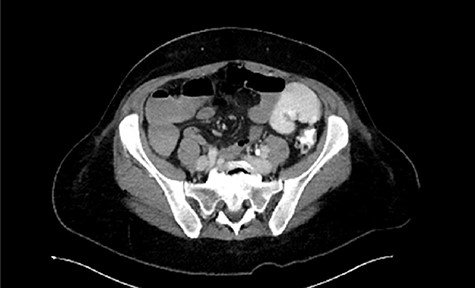

Immediate postoperative course was uneventful until postoperative day (POD)-5 when she experienced multiple watery stools, diffuse abdominal pain, fever (102.6F) and leukocytosis (23000/UL). Clostridium difficile infection was ruled out with a negative stool toxin assay. Her abdominal exam remained nonspecific until POD-6 when she had bilious emesis. A computed tomography (CT) scan revealed perforated diverticulitis with pelvic abscess and multiple colonic diverticulitis with an associated small bowel obstruction (SBO) (Images 1–4). No prior history of diverticulitis was reported.

Sagittal image of colonic diverticuli. S: stomach; Sp: spleen; K: kidney; I: ileum; Blue arrows: multiple colonic diverticuli.